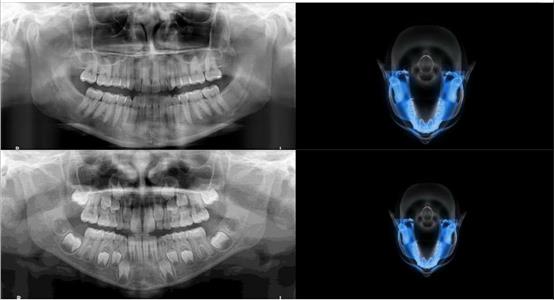

Панорамикс кабинет

За само 13 секунди се добива високо квалитетна ортопантомграфска снимка, странична смнимка, снимка на вилични зглобови, снимка на синуси. Најновиот Kodak панорамикс има 2Д+ програма со која се добиваат 5 пресека во длабочина за прецизна дијагноза и позиција на импактирани заби и други промени. Со квалитетна панорамска снимка нашиот стручен тим ќе постави точна дијагноза и одреди соодветен план на терапија.